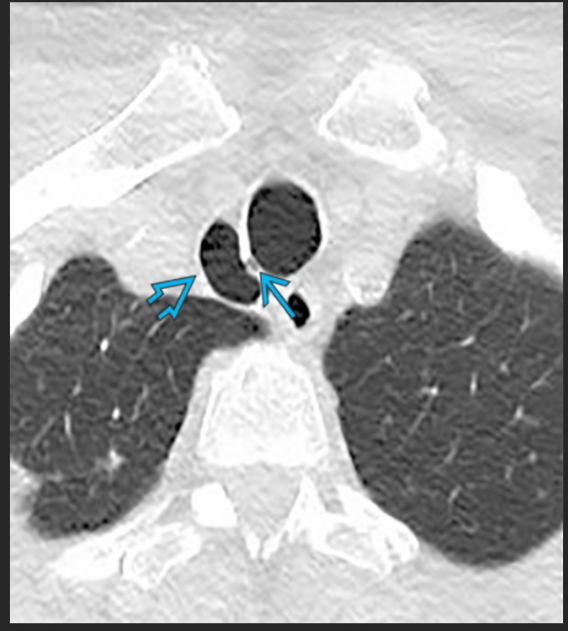

asymptomatic patient

tracheal diverticulum